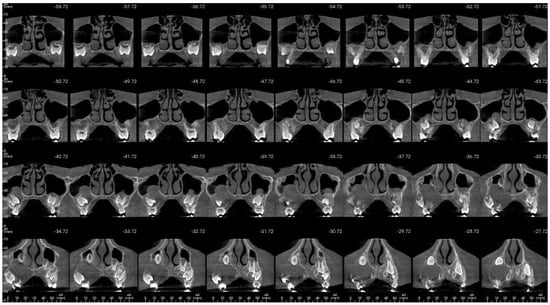

That finding necessitated further diagnostics with CBCT (Figure 4, Figure 5, Figure 6 and Figure 7). A 3D radiograph confirmed a round, well-demarcated, noninflammatory cyst-like lesion extending from Teeth 11 to 15.

CBCT before treatment—coronal view.

Figure 7.

A hypodense focus representing a loss of osseous tissue surrounded the crown of the displaced upper right permanent canine. The unerupted first and second premolars were dislocated and rotated, and Tooth 12 also presented mesiorotation and mesioinclination. The teeth involved in the lesion had open apices and no sign of root resorption. The alveolar bone was deformed, especially in the vestibulopalatal dimension, with a noticeable displacement of the medial interior wall of the right maxillary sinus.